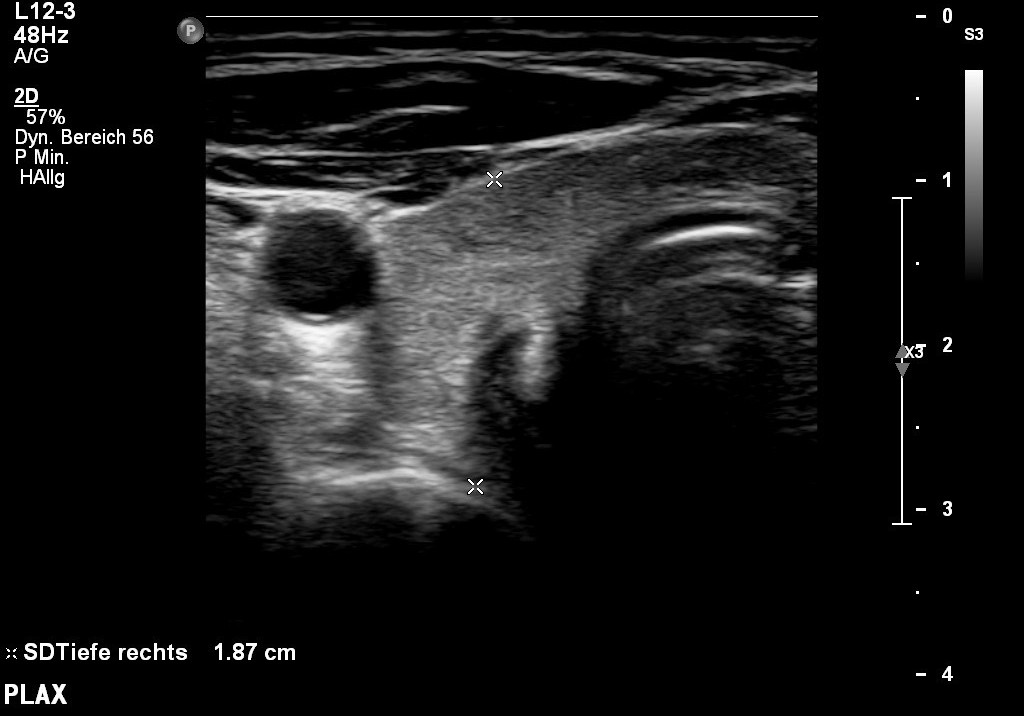

Duplex-Sonographie

Halsgefäße / Abdomen / Schilddrüse